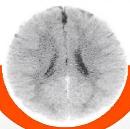

POR DENTRO DO CÉREBRO

Estas são imagens dos cérebros de duas crianças de 3 anos. O menor tamanho e os espaços escuros indicam lacunas no desenvolvimento, causadas pela negligência e pela falta de afeto

Desenvolvimento regular

Extrema negligência